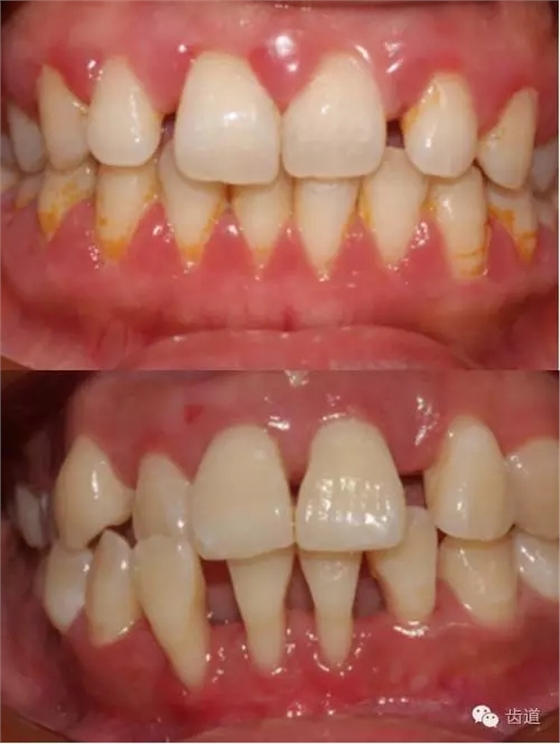

1、口腔衛(wèi)生狀況及局部刺激物(牙菌斑、牙石,不良修復體)

牙石及不良修復體

2、牙齦

(顏色、形狀、質地、退縮、BOP、PD、附著齦)